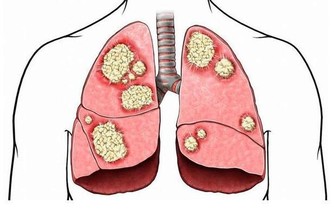

蛋白過多,死得越快。為什麼?很多氨基酸從尿裡排出,影響腎臟;消化不良,又會造成腸道毒素太多。

這也就罷了,關鍵是,孩子正餐還要吃很多肉。在臨床中,經常有幾歲的小女孩,過早乳房發育,甚至形成結節,均與飲食中過多肉蛋奶有很大關係,營養過剩,促使孩子過早發育,過早成熟。